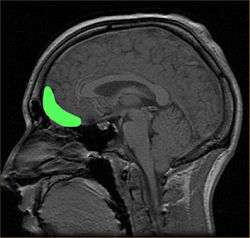

Image of the Brain

Abnormal patterns of brain activity are observed in children with callous-unemotional and psychopathic traits when viewing others in painful situations.